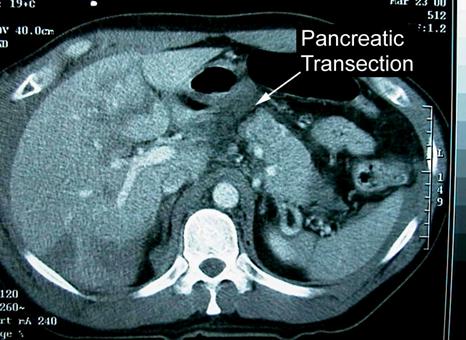

Traumatism abdominal inchis

Leziune de pancreas ( ambele foto)

Traumatism abdominal

inchis

Leziune pancreatica